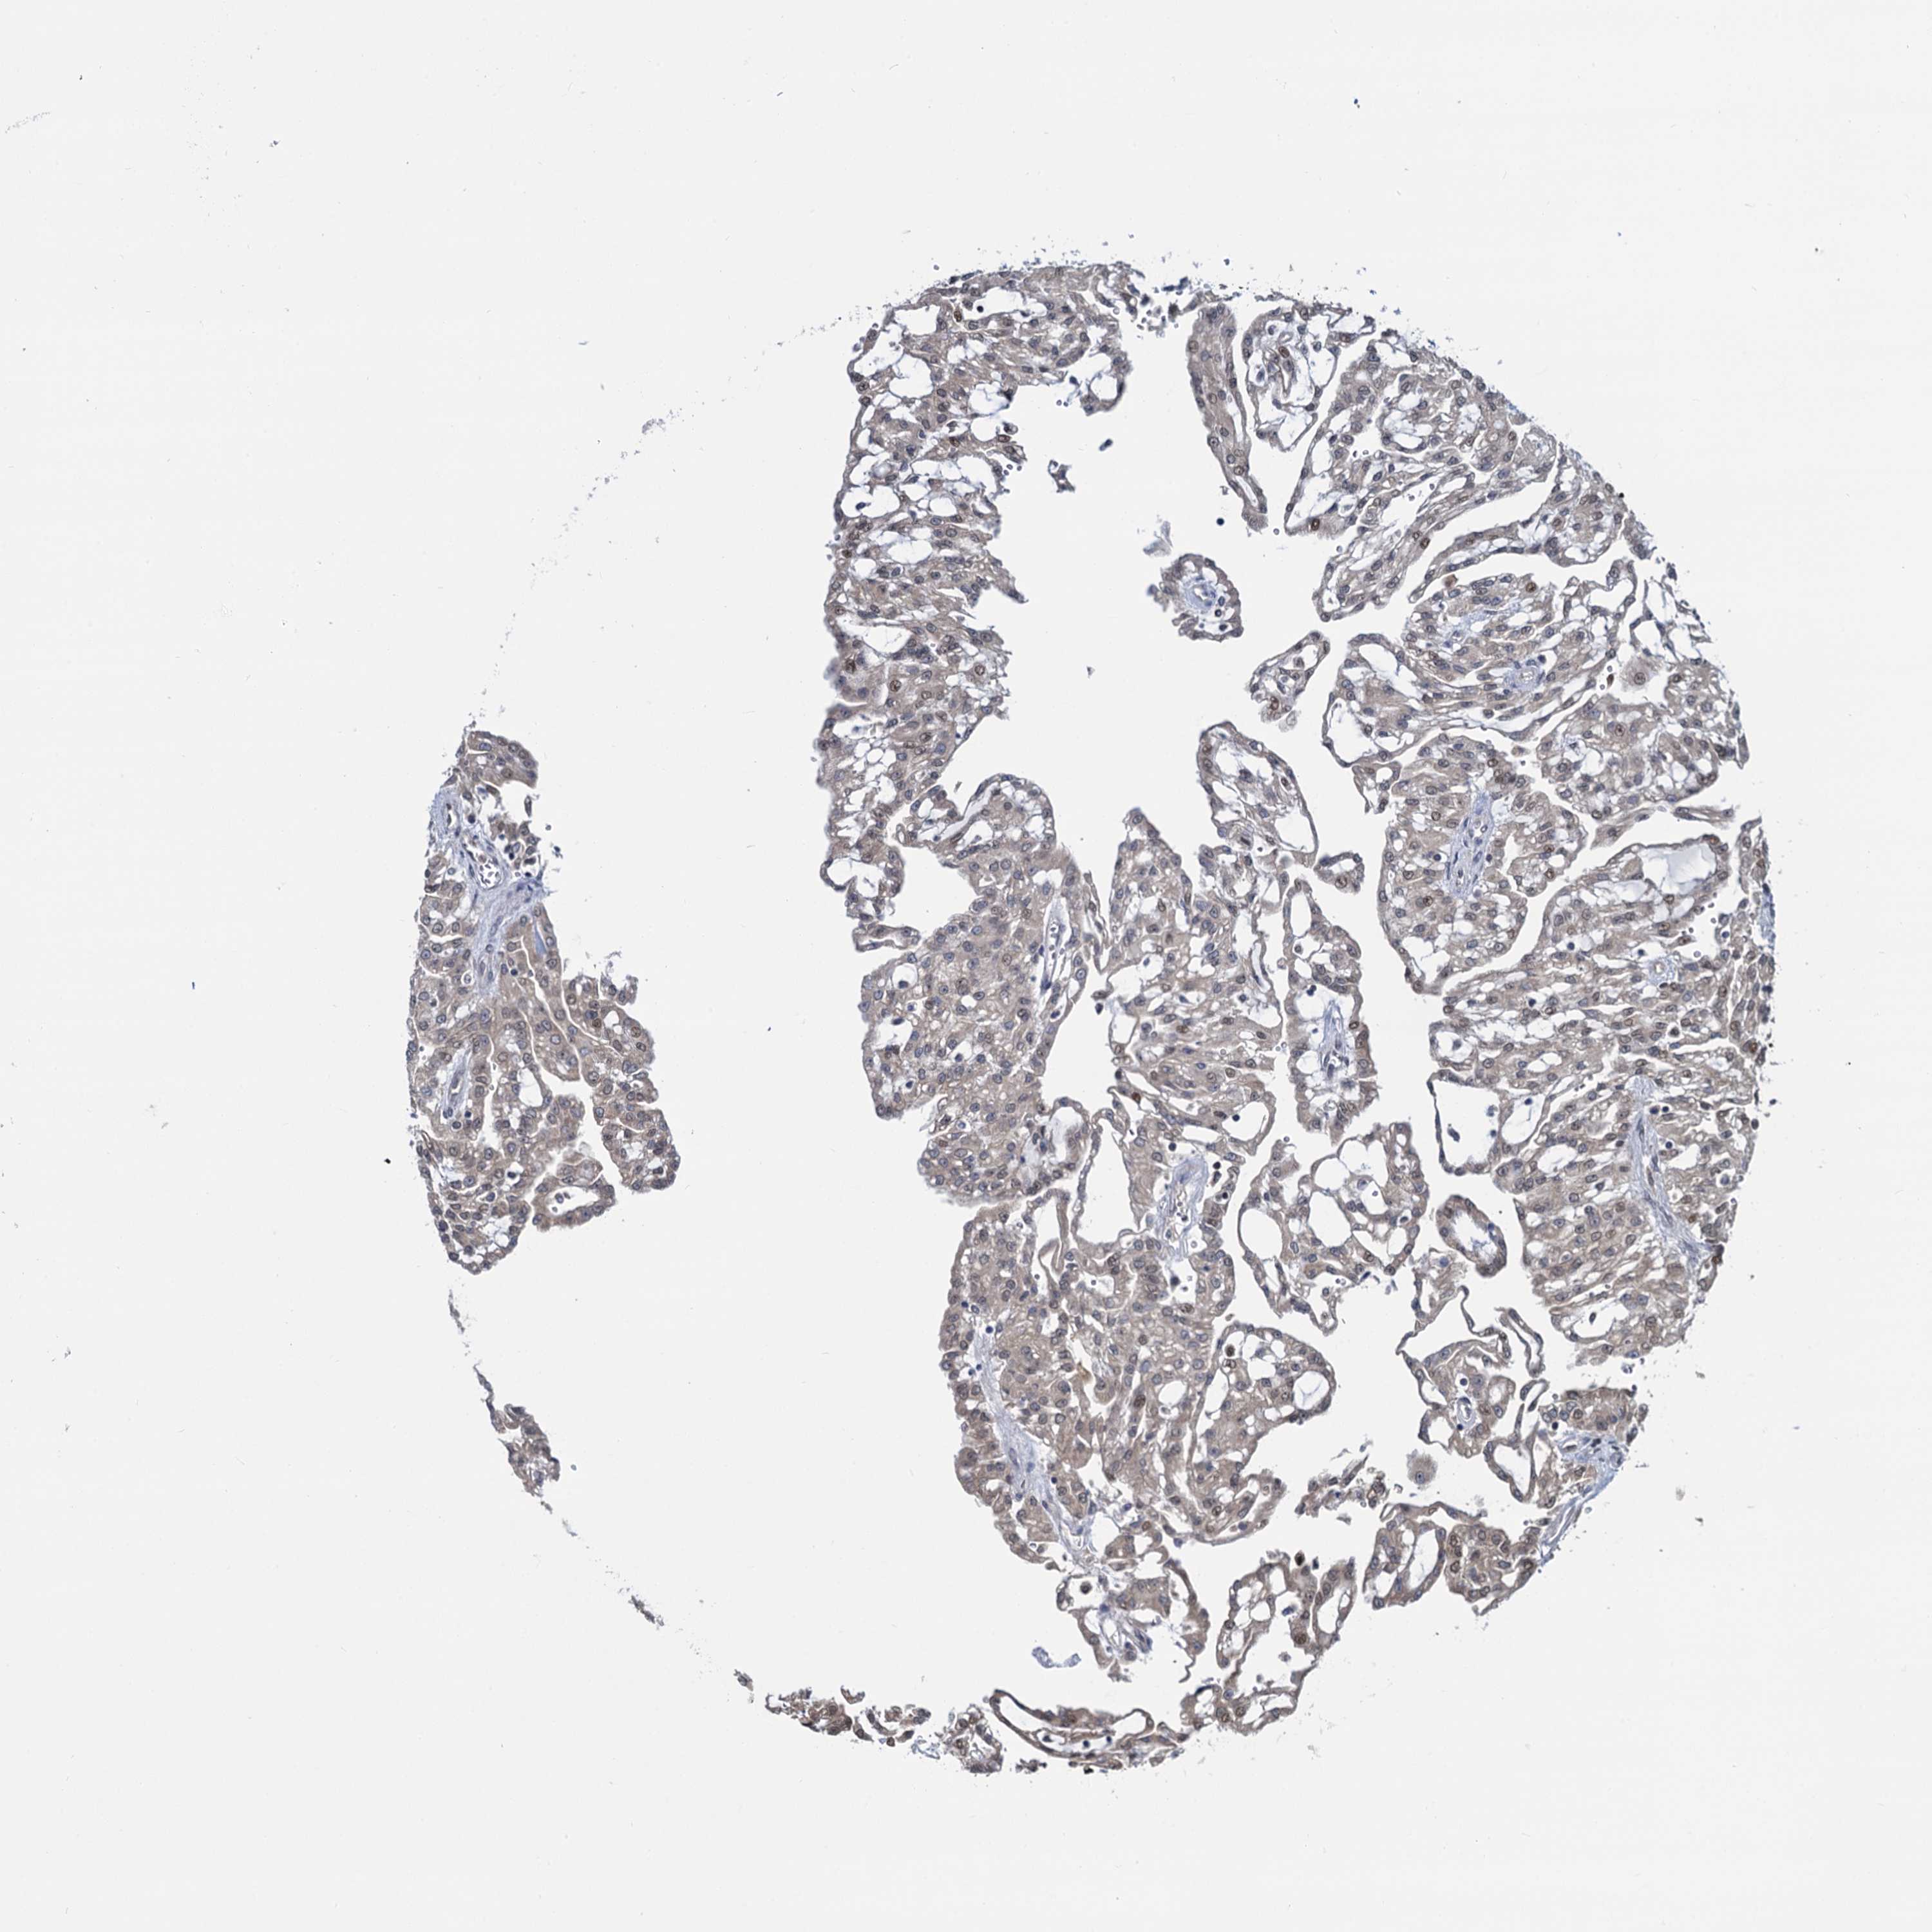

KIDNEY RENAL CLEAR CELL CARCINOMA (VALIDATION) - Interactive survival scatter ploti

The Survival Scatter plot shows the clinical status (i.e. dead or alive) for all individuals in the patient cohort, based on the same data that underlies the corresponding Kaplan-Meier plots. Patients that are alive at last time for follow-up are shown in blue and patients who have died during the study are shown in red.

The x-axis shows the expression levels (FPKM) of the investigated gene in the tumor tissue at the time of diagnosis. The y-axis shows the follow-up time after diagnosis (years). Both axes are complimented with kernel density curves demonstrating the data density over the axes. The top density plot shows the expression levels (FPKM) distribution among dead (red) and alive patients (blue). The right density plot shows the data density of the survived years of dead patients with high and low expression levels respectively, stratified using the cutoff indicated by the vertical dashed line through the Survival Scatter plot. This cutoff is automatically defined based on the FPKM cutoff that minimizes the p-score. The cutoff can be changed by dragging the vertical line or by entering a cutoff value in the square labeled "Current cut-off".

Under the Survival Scatter plot the p-score landscape (black curve; left axis) is shown together with dead median separation (red curve; right axis). Dead median separation is the difference in median mRNA expression between patients who have died with high and low expression, respectively. It is calculated as follows: median FPKM expression of dead patients with high expression - median FPKM expression of dead patients with low expression. This is intended to aid the user in visually exploring custom cutoffs and the associated p-scores and dead median separation.

Individual patient data is displayed and can be filtered by clicking on one or more of the category buttons on the top of the page. Categories describing expression level and patient information include: high, low, alive, dead, female, male and tumor stages. The scale of the x-axis can be toggled between linear and log-scale by clicking on the "x log" button. Mouse-over function shows TCGA ID, patient information and mRNA expression (FPKM) for each patient.

& Survival analysisi

Kaplan-Meier plots summarize results from analysis of correlation between mRNA expression level and patient survival. Patients were divided based on level of expression into one of the two groups "low" (under cut off) or "high" (over cut off). X-axis shows time for survival (years) and y-axis shows the probability of survival, where 1.0 corresponds to 100 percent.

RNF125 is not prognostic in Kidney Renal Clear Cell Carcinoma (validation)

Best expression cut offi

Based on the FPKM value of each gene, patients were classified into two groups and association between prognosis (survival) and gene expression (FPKM) was examined. The best expression cut-off refers the FPKM value that yields maximal difference with regard to survival between the two groups at the lowest log-rank P-value. Best expression cut-off was selected based on survival analysis .

When clicking on this number, the vertical dashed line indicating cut-off, the interactive survival plot, and the Kaplan-Meier curve will be adjusted to show results based on the best expression cut-off.

: 3.71

TCGA RNA samplesi

RNA-seq data is reported as average FPKM (number Fragments Per Kilobase of exon per Million reads), generated by the The Cancer Genome Atlas (TCGA) .

Normal distribution across the dataset is visualized with box plots, shown as median and 25th and 75th percentiles. Points are displayed as outliers if they are above or below 1.5 times the interquartile range. FPKM values of the individual samples are presented next to the box plot.

Average pTPM 3.5

Number of samples 100